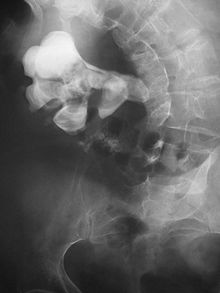

Otherwise a noncontrast helical CT scan with 5 millimeters (0.2 in) sections is the diagnostic method to use to detect kidney stones and confirm the diagnosis of kidney stone disease.[13][47][51][52][7] Near all stones are detectable on CT scans with the exception of those composed of certain drug residues in the urine,[53] such as from indinavir. Calcium-containing stones are relatively radiodense, and they can often be detected by a traditional radiograph of the abdomen that includes the kidneys, ureters, and bladder (KUB film).[53] Some 60% of all renal stones are radiopaque.[51][54] In general, calcium phosphate stones have the greatest density, followed by calcium oxalate and magnesium ammonium phosphate stones. Cystine calculi are only faintly radiodense, while uric acid stones are usually entirely radiolucent.[55]

Where a CT scan is unavailable, an intravenous pyelogram may be performed to help confirm the diagnosis of urolithiasis. This involves intravenous injection of a contrast agent followed by a KUB film. Uroliths present in the kidneys, ureters, or bladder may be better defined by the use of this contrast agent. Stones can also be detected by a retrograde pyelogram, where a similar contrast agent is injected directly into the distal ostium of the ureter (where the ureter terminates as it enters the bladder).[51]

Bilateral kidney stones can be seen on this KUB radiograph. There are phleboliths in the pelvis, which can be misinterpreted as bladder stones.